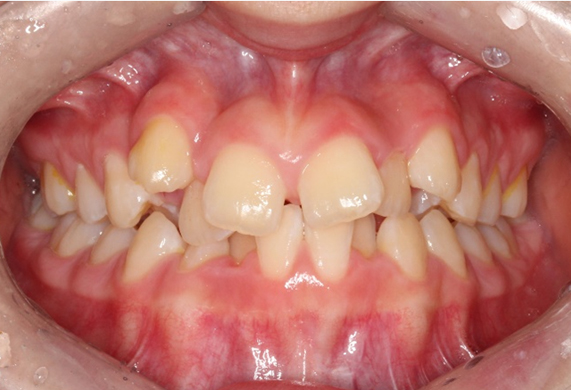

덧니 교정

치아가 나올 때 턱뼈가 작거나 치아 사이의 공간이 부족할 때 치아 배열에서 벗어난 곳에 나는 치아를 말합니다. 특정 치아 뿐 아니라 여러 치아가 전체적으로 조금씩 삐뚠 치아도 일종의 덧니라고 볼 수 있습니다.

덧니 교정 CASE